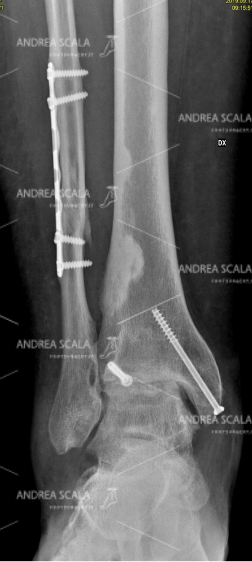

La RXgrafia anteriore mostra la frattura tri-malleolare con lesione della capsula e dei legamenti. Una giovane paziente ha subito questa grave frattura a 34 anni.

La RXgrafia laterale mostra la frattura tri-malleolare con lesione della capsula e dei legamenti. Si nota la grave scomposizione della frattura. In questi casi si deve capire che lo schiacciamento subito dalla cartilagine è inevitabile.

La RXgrafia anteriore mostra che la frattura tri-malleolare è stata operata con impianto di placca e viti. Il risultato post-operatorio è buono e l’articolazione sembra ben ricostruita.

La RXgrafia laterale mostra che la frattura tri-malleolare è stata operata. Il perone è stato ricomposto con placca e viti. Il malleolo tibiale ed il terzo malleolo sono stati ricomposti con viti.